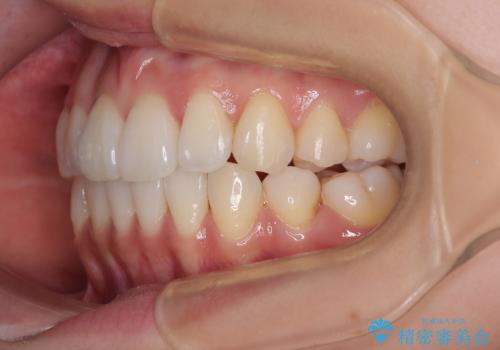

1. 抜歯矯正の軽度後戻りを解消 インビザライン矯正の治療前

2. 抜歯矯正の軽度後戻りを解消 インビザライン矯正の治療中

3. 抜歯矯正の軽度後戻りを解消 インビザライン矯正の治療後